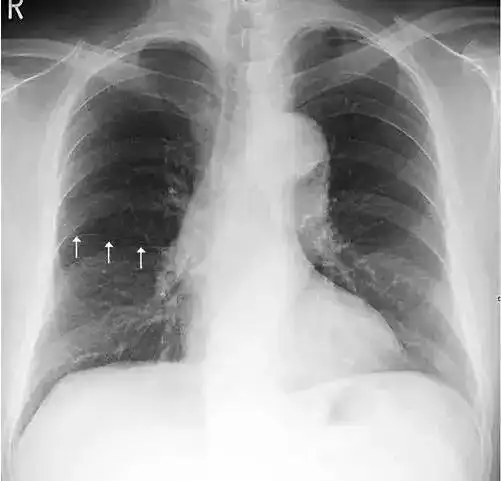

影像解剖入门正常胸片怎么看